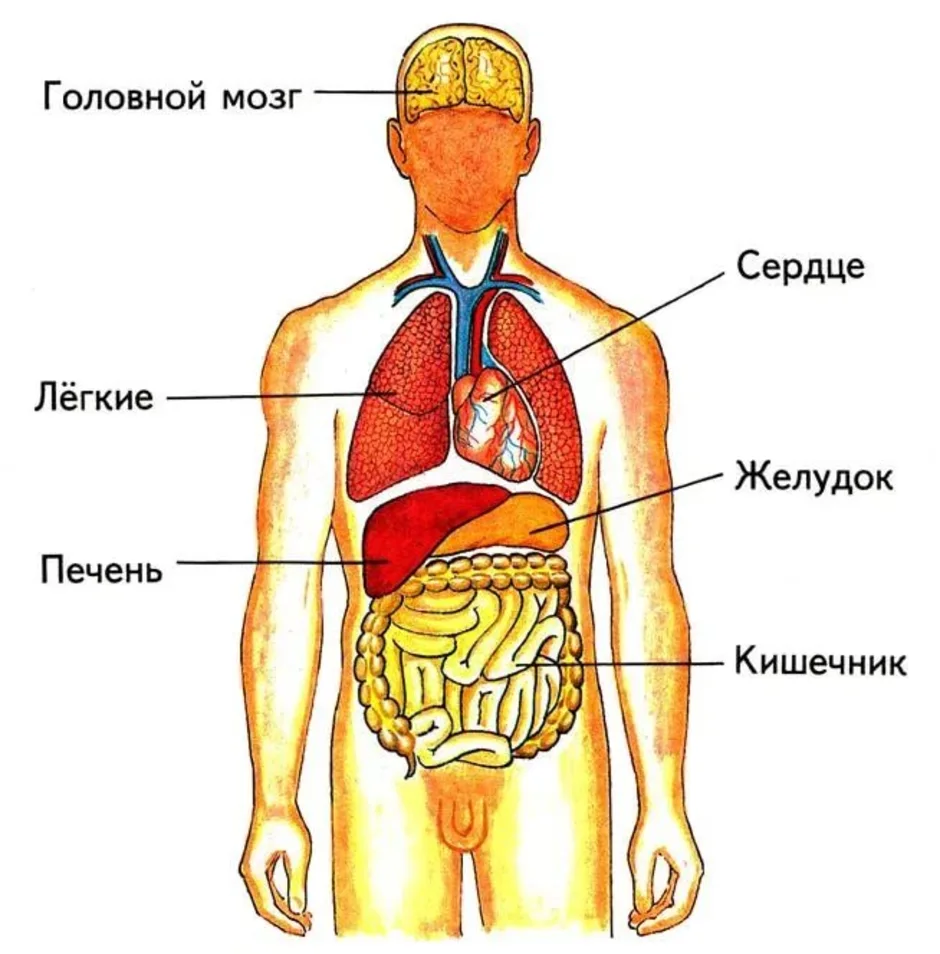

Анатомия Сердца: Расположение и Функции